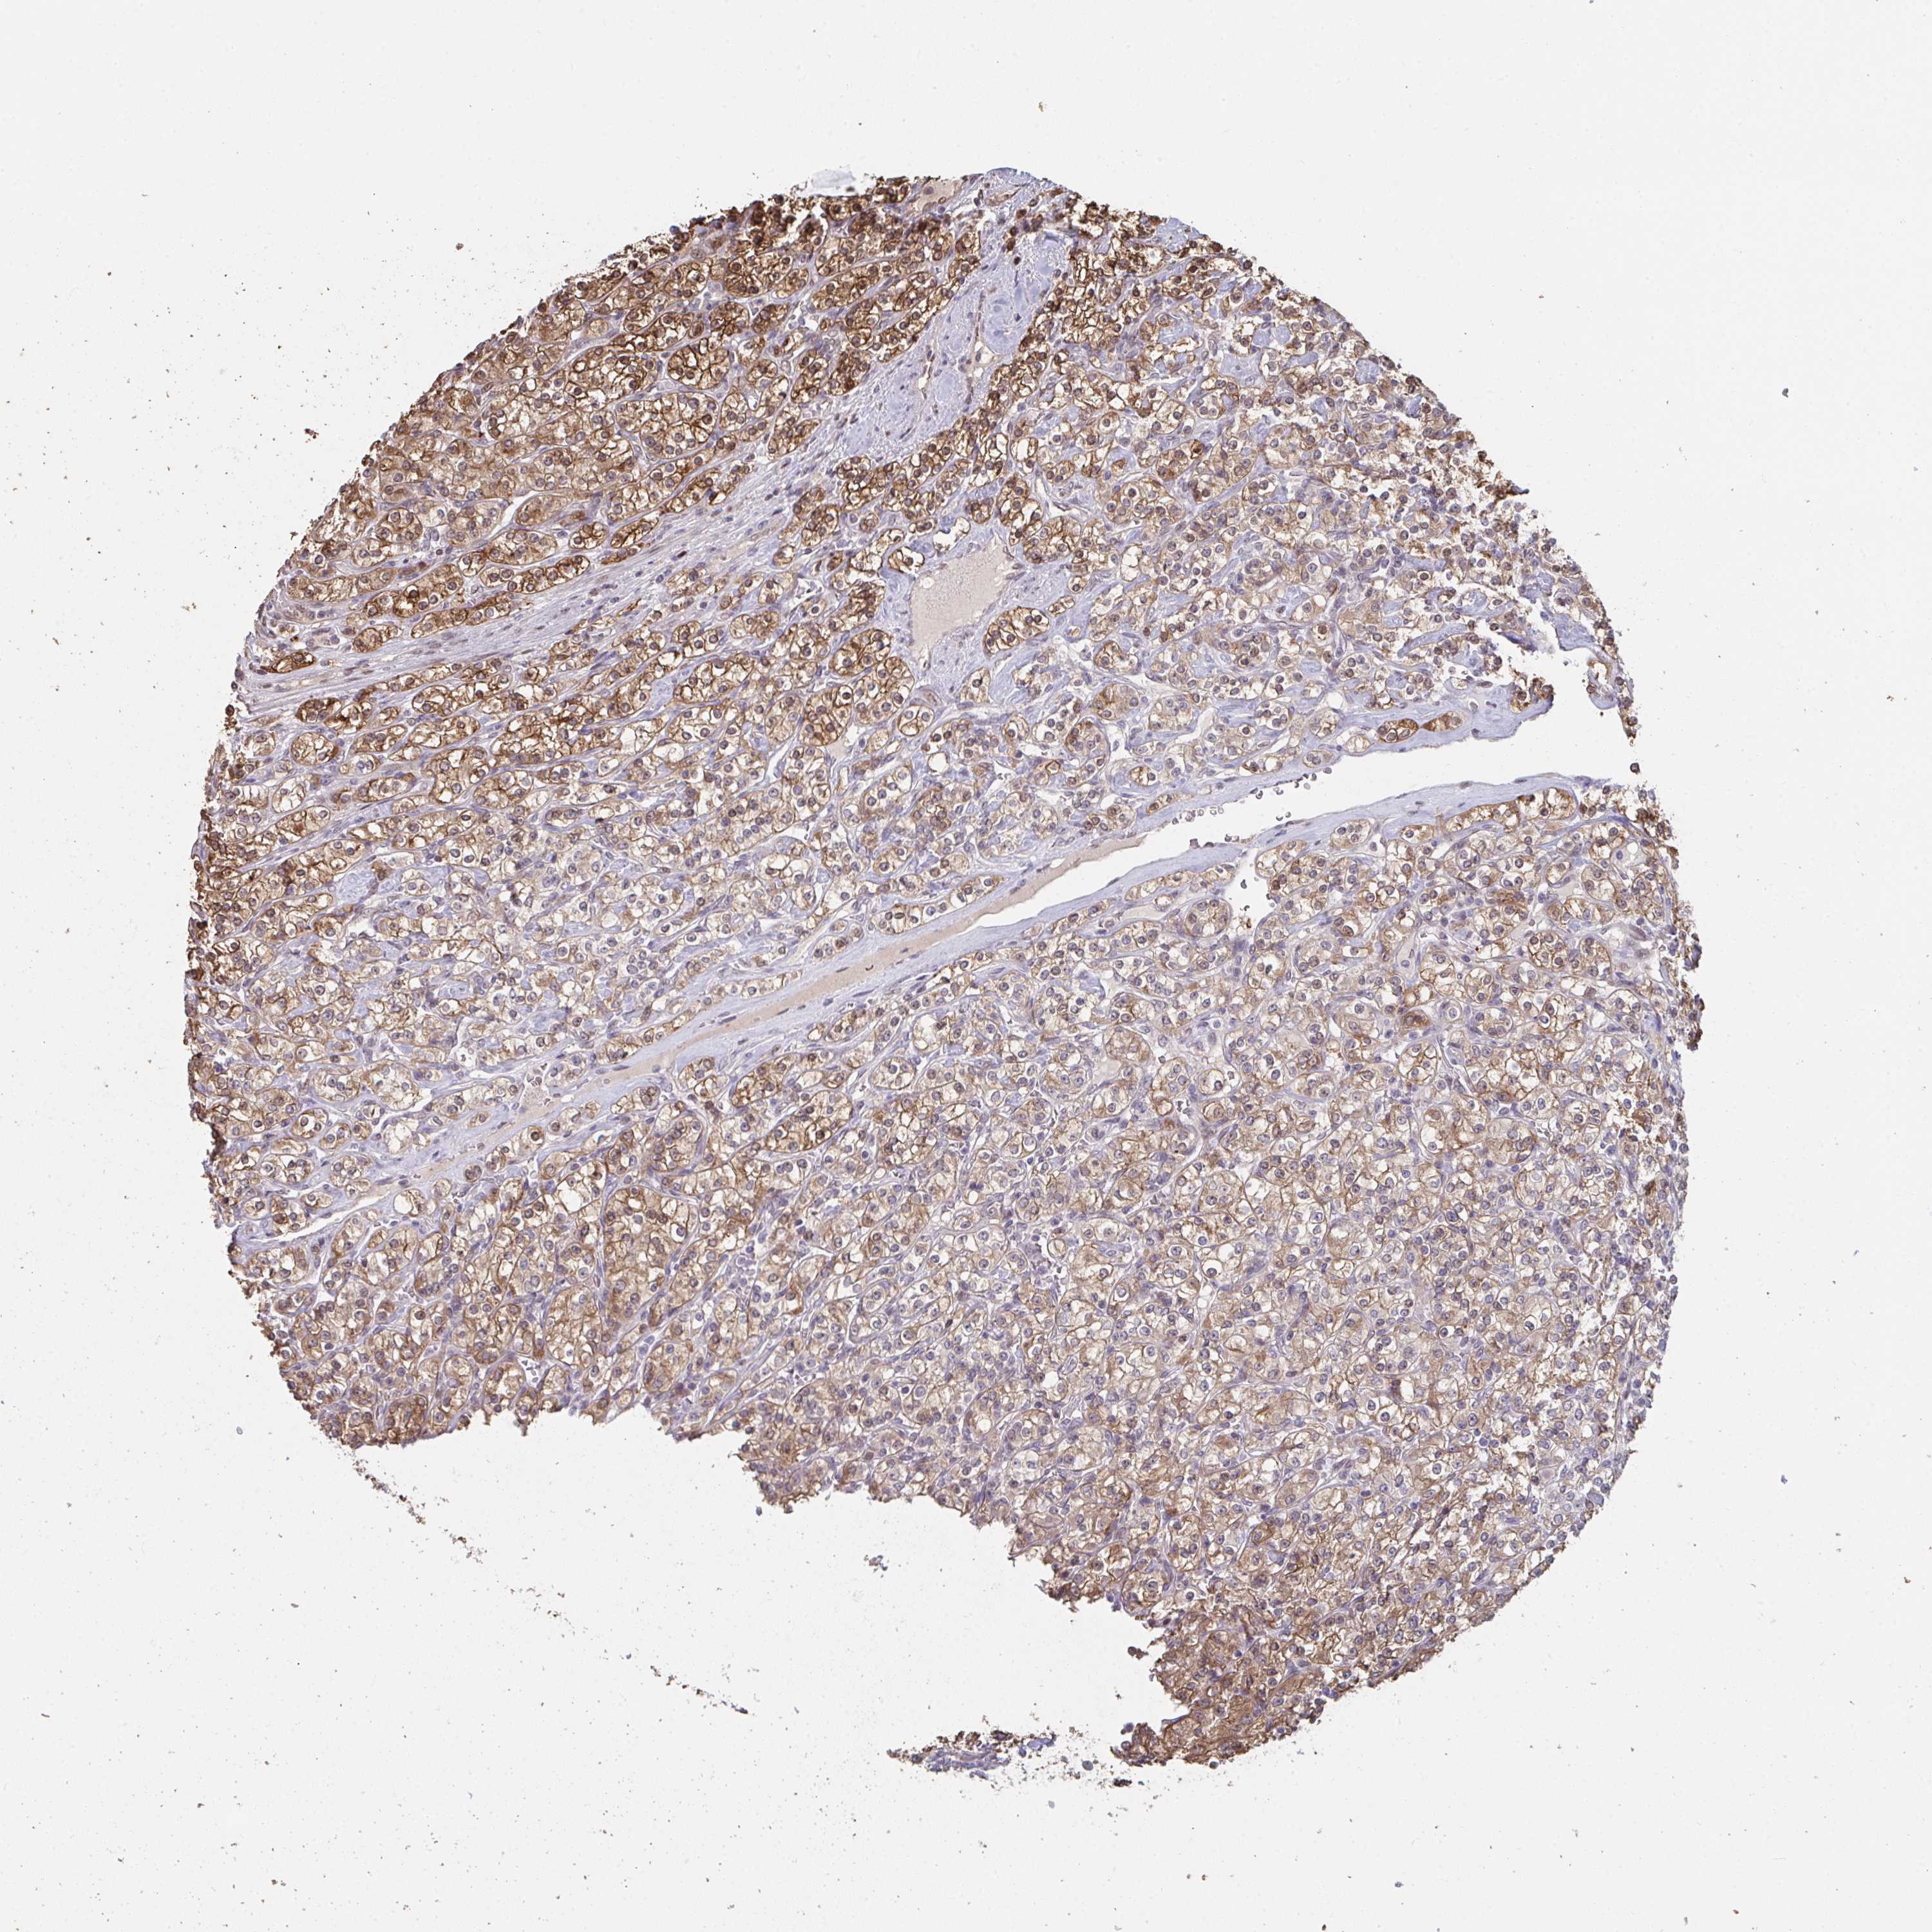

KIDNEY RENAL CLEAR CELL CARCINOMA (VALIDATION) - Interactive survival scatter ploti

The Survival Scatter plot shows the clinical status (i.e. dead or alive) for all individuals in the patient cohort, based on the same data that underlies the corresponding Kaplan-Meier plots. Patients that are alive at last time for follow-up are shown in blue and patients who have died during the study are shown in red.

The x-axis shows the expression levels (FPKM) of the investigated gene in the tumor tissue at the time of diagnosis. The y-axis shows the follow-up time after diagnosis (years). Both axes are complimented with kernel density curves demonstrating the data density over the axes. The top density plot shows the expression levels (FPKM) distribution among dead (red) and alive patients (blue). The right density plot shows the data density of the survived years of dead patients with high and low expression levels respectively, stratified using the cutoff indicated by the vertical dashed line through the Survival Scatter plot. This cutoff is automatically defined based on the FPKM cutoff that minimizes the p-score. The cutoff can be changed by dragging the vertical line or by entering a cutoff value in the square labeled "Current cut-off".

Under the Survival Scatter plot the p-score landscape (black curve; left axis) is shown together with dead median separation (red curve; right axis). Dead median separation is the difference in median mRNA expression between patients who have died with high and low expression, respectively. It is calculated as follows: median FPKM expression of dead patients with high expression - median FPKM expression of dead patients with low expression. This is intended to aid the user in visually exploring custom cutoffs and the associated p-scores and dead median separation.

Individual patient data is displayed and can be filtered by clicking on one or more of the category buttons on the top of the page. Categories describing expression level and patient information include: high, low, alive, dead, female, male and tumor stages. The scale of the x-axis can be toggled between linear and log-scale by clicking on the "x log" button. Mouse-over function shows TCGA ID, patient information and mRNA expression (FPKM) for each patient.

& Survival analysisi

Kaplan-Meier plots summarize results from analysis of correlation between mRNA expression level and patient survival. Patients were divided based on level of expression into one of the two groups "low" (under cut off) or "high" (over cut off). X-axis shows time for survival (years) and y-axis shows the probability of survival, where 1.0 corresponds to 100 percent.

ACD is not prognostic in Kidney Renal Clear Cell Carcinoma (validation)

Best expression cut offi

Based on the FPKM value of each gene, patients were classified into two groups and association between prognosis (survival) and gene expression (FPKM) was examined. The best expression cut-off refers the FPKM value that yields maximal difference with regard to survival between the two groups at the lowest log-rank P-value. Best expression cut-off was selected based on survival analysis .

When clicking on this number, the vertical dashed line indicating cut-off, the interactive survival plot, and the Kaplan-Meier curve will be adjusted to show results based on the best expression cut-off.

: 10.36

P scorei

Log-rank P value for Kaplan-Meier plot showing results from analysis of correlation between mRNA expression level and patient survival.

N/A

TCGA RNA samplesi

RNA-seq data is reported as average FPKM (number Fragments Per Kilobase of exon per Million reads), generated by the The Cancer Genome Atlas (TCGA) .

Normal distribution across the dataset is visualized with box plots, shown as median and 25th and 75th percentiles. Points are displayed as outliers if they are above or below 1.5 times the interquartile range. FPKM values of the individual samples are presented next to the box plot.

Average pTPM 13.5

Number of samples 100